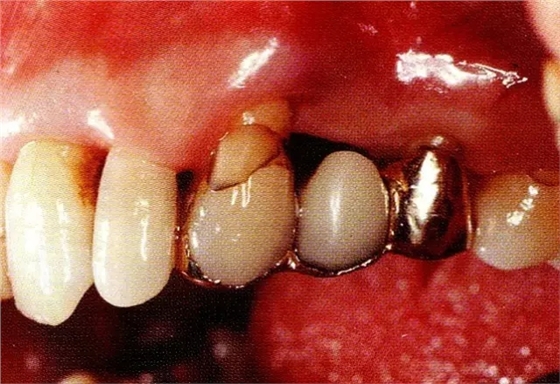

▲圖8-1 52歲,上班族,女性。來院主訴是左上橋體下部有空隙。

▲圖8-2初診時(shí)的x片。尖牙遠(yuǎn)中確認(rèn)有垂直性骨缺損。

▲圖8-3進(jìn)行全厚瓣翻瓣,將根表面的沉積物、骨缺損的肉芽組織徹底清除,確認(rèn)牙槽骨形態(tài),可看到從頰側(cè)到遠(yuǎn)中存在垂直性和水平性的骨缺損。